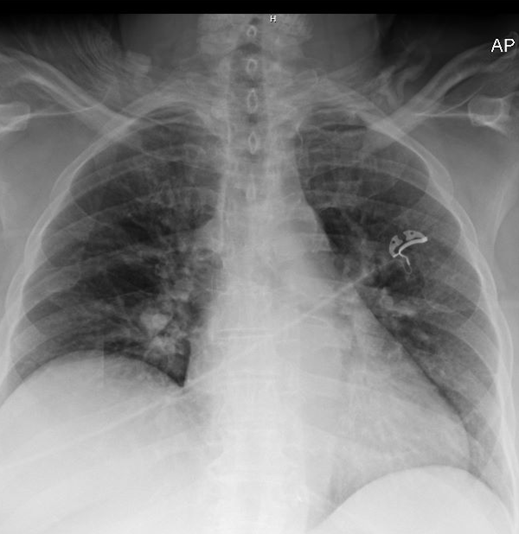

History was obtained from the patient and her daughter at bedside. The patient is drowsy but able to say that her abdomen hurts and that she has not been able to urinate for a few days. She has had a few loose stools. She had dental surgery about a week ago and reports decreased PO intake. She has not had any fevers, dental pain or swelling. She does not have any chest pain or shortness of breath. Her daughter confirms this history. She was found to have a past medical history of CAD, HTN, non-insulin dependent DM, CKD, previous renal stones and ureteral stents (now removed) and a previous sleeve gastrectomy.

On exam the patient is ill appearing, awake, alert but mildly confused. She is protecting her airway and is able to speak in full sentences without respiratory distress. She does not have any focal neurological deficits. Her abdomen has mild diffuse tenderness. Her oropharynx is clear, she is edentulous. She does not have any trismus, stridor or evidence of mandibular swelling or tenderness over the site of her reported dental surgery. She has a foley in place with <5 cc of cloudy urine in the tubing.

A non-contrast CT abdomen/pelvis was obtained which is shown below:

IMPRESSION:

Nonspecific stranding adjacent to bilateral kidneys without

hydronephrosis.

Stable dilation of the extrahepatic bile duct. Correlate with biliary

enzymes if there is clinical concern for obstruction.

The foley catheter was in the bladder and the bladder was empty. The foley catheter was flushed without any urine output.